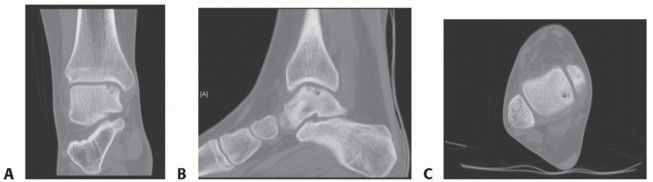

Demonstrates associated marrow edema that may lead to overestimation of the OLT's size Computed tomography (CT) (

FIG 2

)

Ideal for characterizing OLT, particularly large volume defects Defines OLT size without distraction of associated marrow edema

Defines the character of the OLT and extent of its involvement in the talar dome Diagnostic injection

FIG 2 • CT. A. Coronal view with medial OLT that approaches talar shoulder but appears contained. B. Sagittal view demonstrating rather medial OLT. C. Axial view with posteromedial OLT.